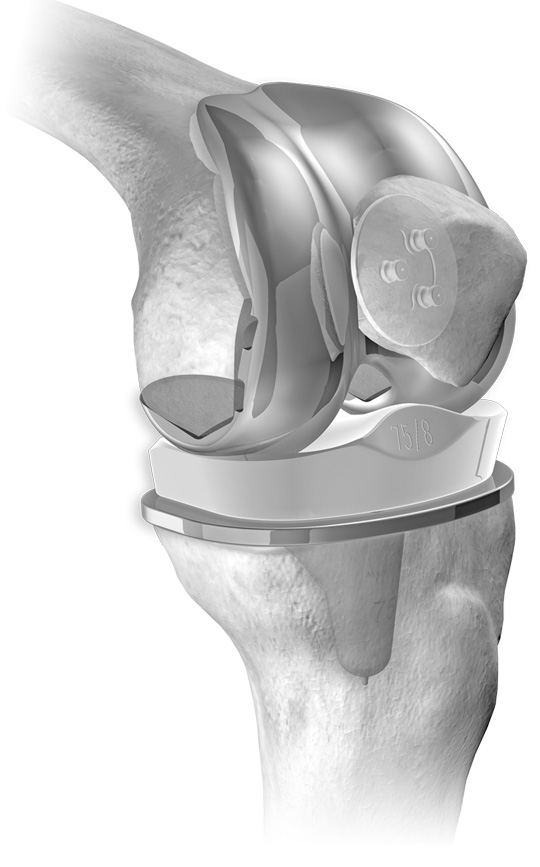

Surgical procedure involves replacing the arthritic surfaces of the knee with metal and plastic implants.

A total knee arthroplasty is composed of a femoral cap, a tibial tray and an insert made of polyethylene.

Fixation of the componets can be achieved with or without bone cement.

X ray and example of an implanted total knee arthoplasty.